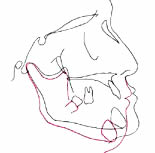

頭の骨や顔の輪郭を分析することで理想の咬み合わせの高さを知ることができます。 鼻・上下の唇・下あごといった顔面上の任意の点や高さを計測して理想的な位置を調べるのです。

古い入れ歯では 下あごは前に出ています (黒線)

新しい入れ歯を 入れたときの変化 (赤い線)